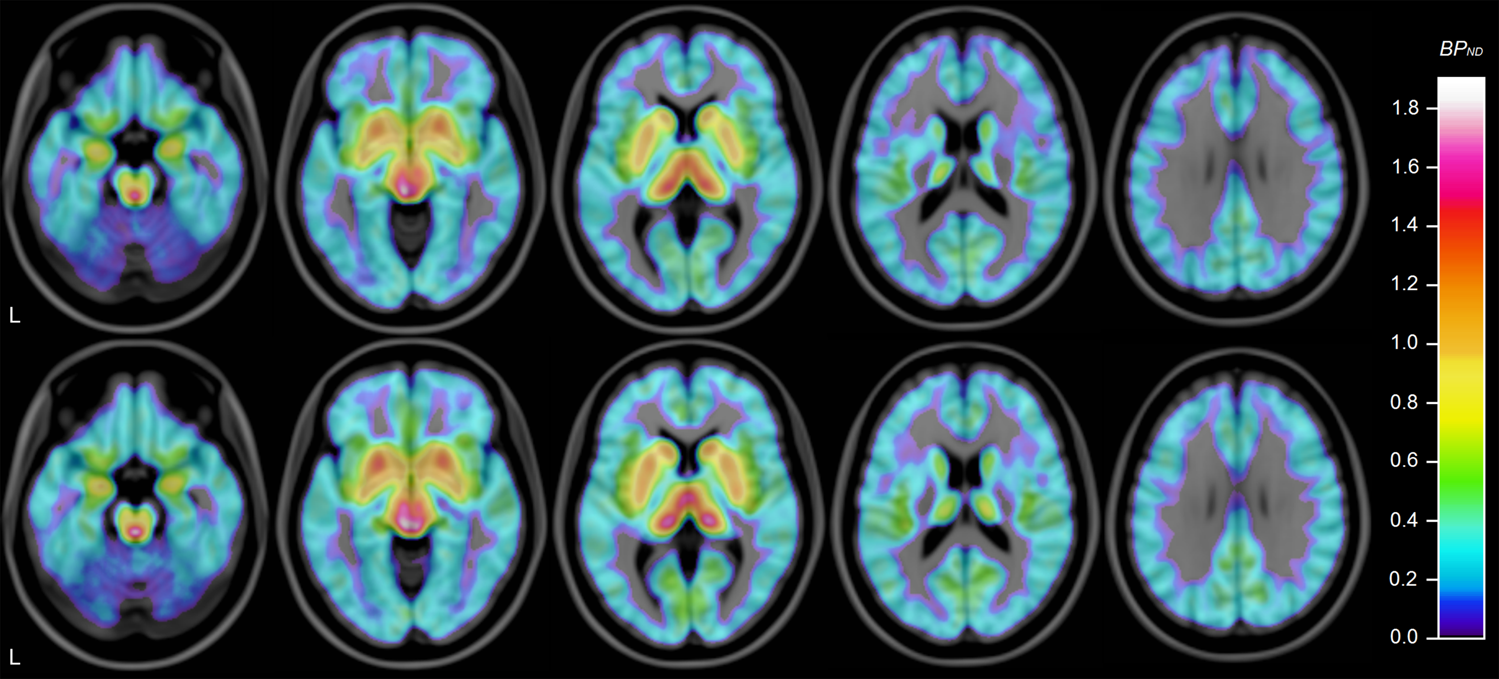

Fig. 2: Mean 5-HTT availability in ASD and control group.

Average of individual parametric images created using wavelet-aided parametric imaging [89], normalized to MNI-152 template using FSL 5.0 (FMRIB, Oxford, UK) and overlaid on MRI template. Subjects with ASD above, control subjects below. Horizontal slices, MNI coordinates (mm) z = −20/−8/4/16/28. “L” indicates left.